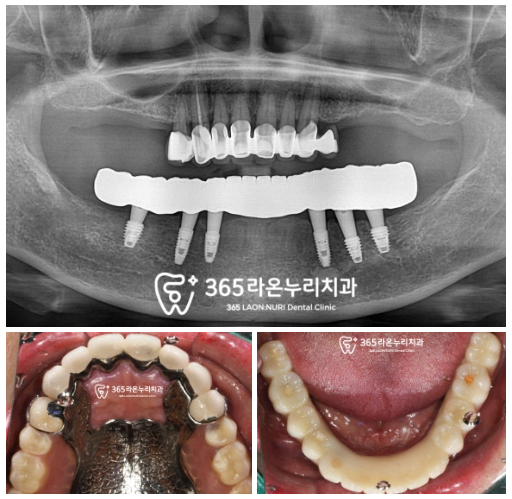

■ 4. 적응 기간

이렇게 전체 임플란트를 하신 환자는

일정기간동안 적응하는 과정이 필요합니다.

아무리 픽스처를 잘 식립했다 하더라도

상부에 보철이 들어가게되면

약간의 어색함과 불편감이 동반되기 때문에

여러번 세밀한 조정을 해드리고 있는데요,

이 케이스에서도 두번에 걸쳐

상악의 틀니와 하악의 임플란트가

서로 조화롭게 어울릴 수 있도록 도와드렸습니다.

환자의 안모와 어울릴 수 있는

크기와 형태를 만들어드렸으며

웃었을때 이가 보이는 정도,

스마일 라인, 턱관절의 편안함 같은

여러 요소를 고려하여 수정과정을 거쳤기에

만족스러운 결과를 기대할 수 있겠네요.

이제는 한결 편안하고

식사도 잘 하고 계시다하셨으며,

치료 과정중에서도

사용감이 워낙 좋아서

힘들지 않게 진료 받았던 덕에

현재는 상악도 틀니 대신 임플란트로

바꿔달라 하셔서 진행중에 있답니다.^^